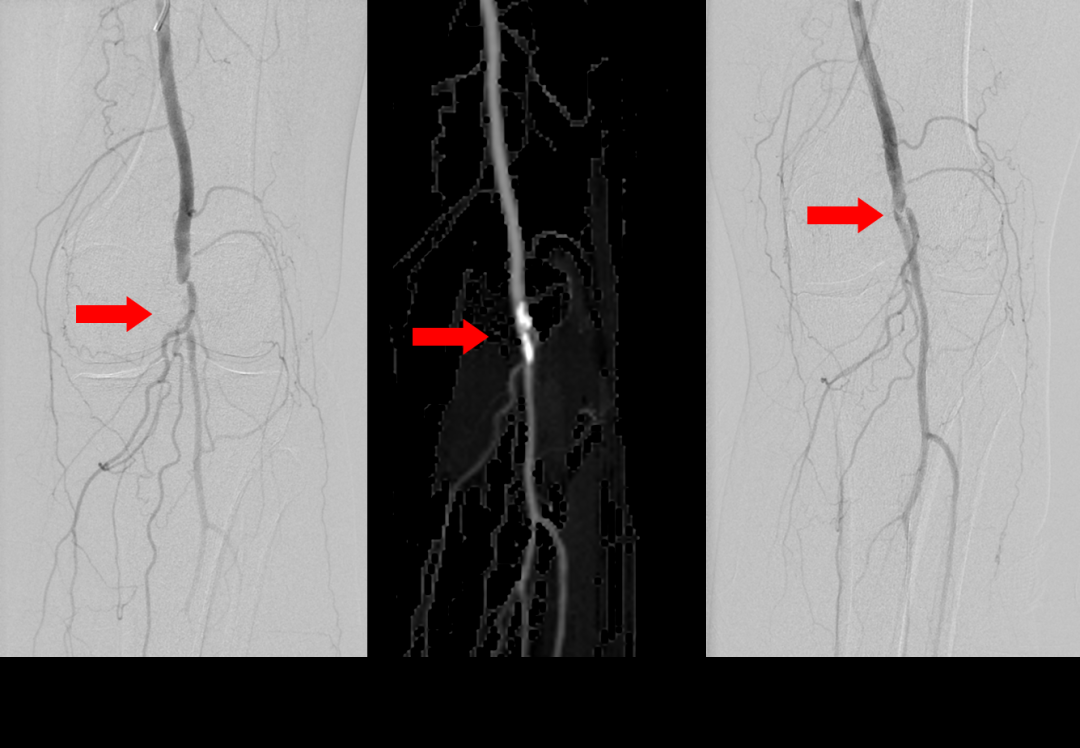

蔡主任先通過局麻下的血管介入手術(shù),用球囊擴(kuò)張打通堵塞的腘動脈,恢復(fù)腿部供血;針對難愈的燙傷傷口,由尚春波醫(yī)生做清創(chuàng)術(shù)+VSD負(fù)壓引流,術(shù)后由尚醫(yī)生和鄧彩云護(hù)士為王奶奶細(xì)致?lián)Q藥直至愈合。